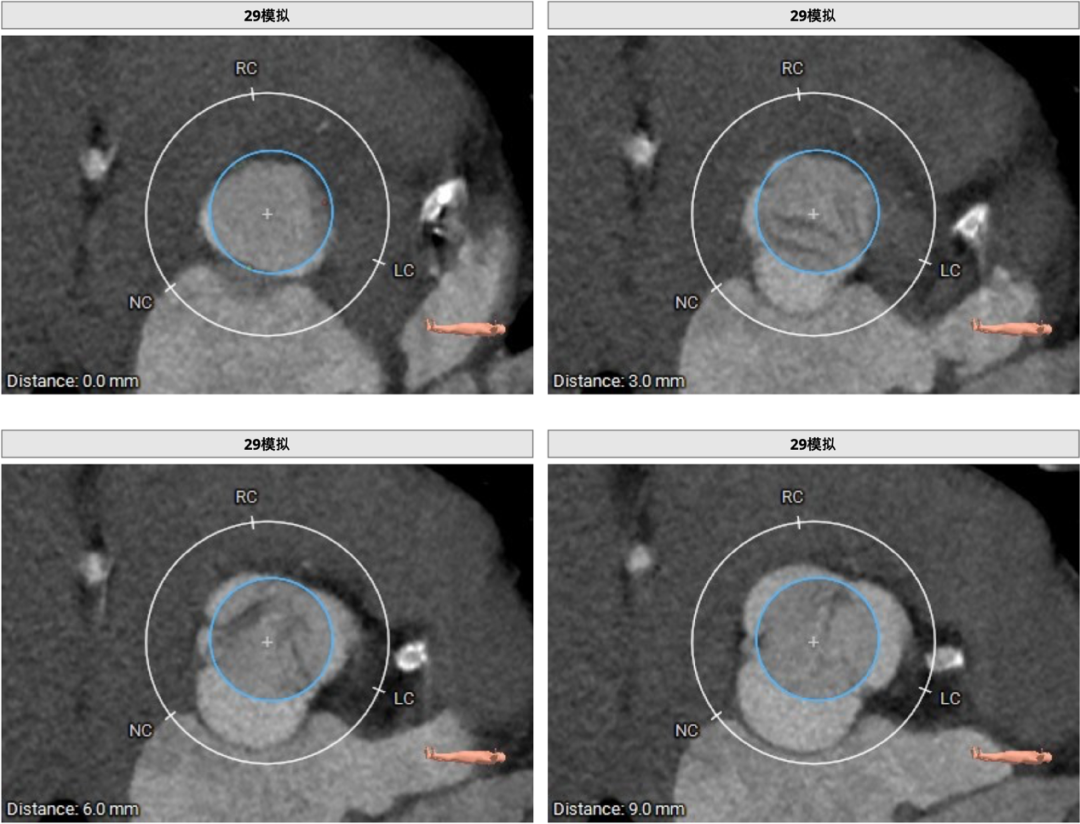

患者主动脉瓣三叶式,瓣叶基本等大,瓣叶增厚,瓣叶未见明显钙化。主动脉瓣环周长折算直径约29.3mm:

29mm瓣膜模拟效果: